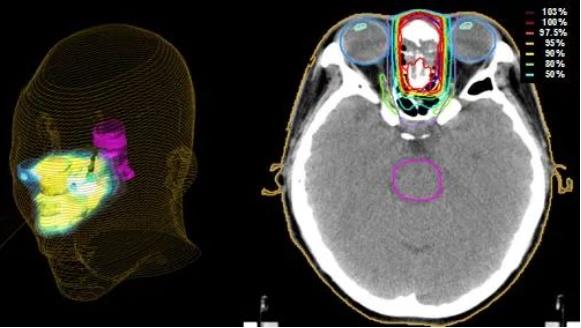

日本质子治疗:头颈癌

头颈癌是指发生在面部和颈部的恶性肿瘤,是指从面部到颈部,大致是头部下方到锁骨区间,主要包括耳、鼻、鼻窦... -